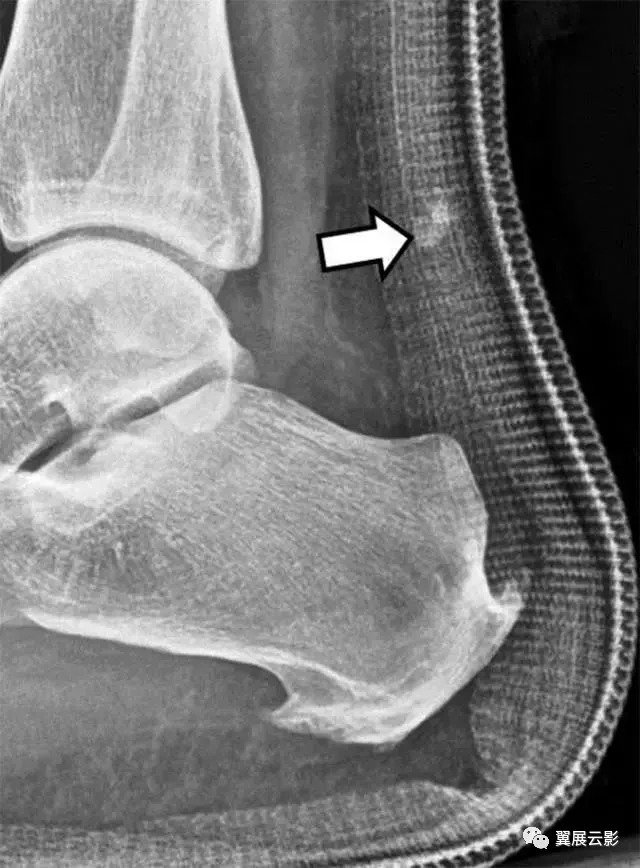

图4A-男,43岁,从马身上掉下来,经历过疼痛,踝关节背部出现瘀伤。A,在损伤后2天获得的X线照片显示了在关节上方约5cm处的跟腱中的骨片(箭头)。